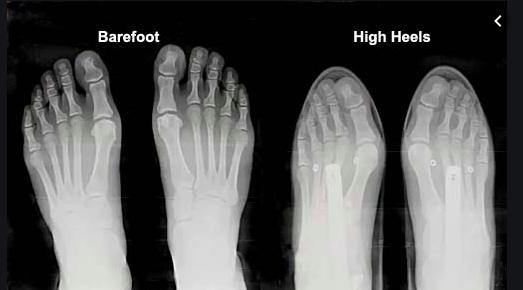

genetika moze ovplyvnit to, ze si na to nachylnejsia. halux vznika vtedy, ked je palec neprirodzene uzkou obuvou tlaceny k ostatnym prstom a tym sa postupne mechanicky vytlaca ta bocna kost von - to je halux. pokial ma noha dostatocny priestor na pohyb, tak nie je dovod vzniku haluxu.

na tomto obrazku to pekne vidis